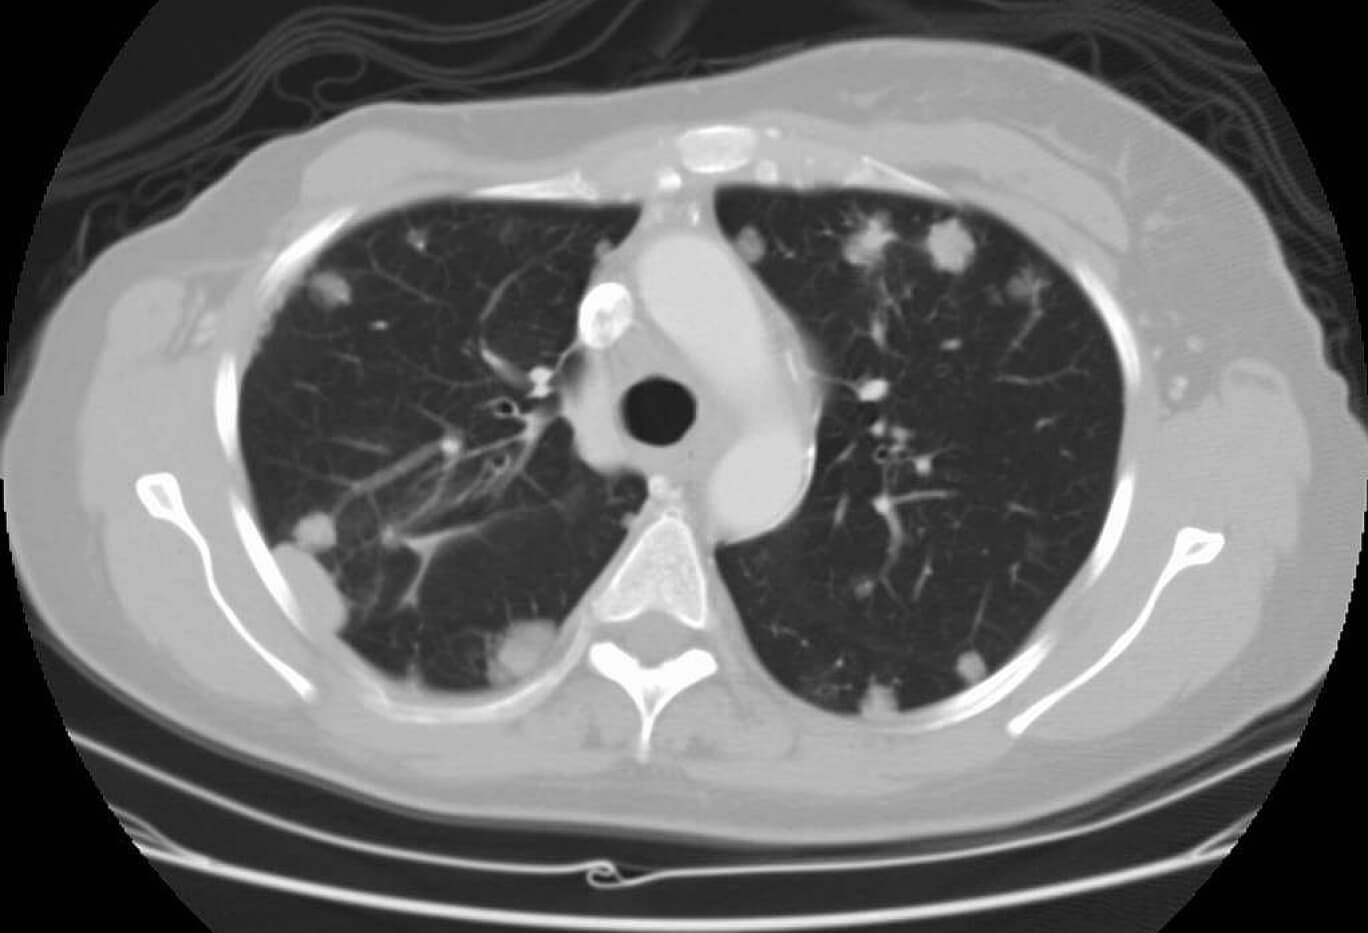

Пациентка перенесла коронавирусную инфекцию средней степени тяжести осложненную двусторонней пневмонией. По данным МСКТ, выполненной без контрастирования, выявлено множество очагов до 1,5 см. При выписке из инфекционного стационара пациентка консультирована онкологом. Рекомендовано обследование в объеме компьютерной томографии с внутривенным контрастированием органов грудной клетки, брюшной полости и малого таза.

Рис. 1 — КТ органов грудной клетки с контрастированием. Отмечается полисегментарное вторичное поражение обоих легких, с учетом анамнеза, вероятно, соответствуют mts рака молочной железы.